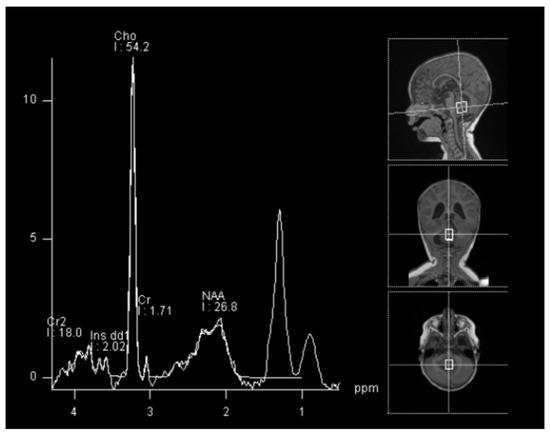

The child was 9 months old with eutocic delivery at 40 gestation weeks, and, according to the parents started to develop ataxia and hypotonia at 6 months old. She developed repeated morning and orthostatic vomiting. The head circumference was at the 98th percentile (46.5 cm), and a cerebral ultrasound (US) showed enlarged lateral ventricles (Figure 1).

Figure 1.

Sagittal and coronal US showing dilated lateral ventricles. Echocolordoppler showed augmented resistance and pulsatility indexes, speaking in favor of augmented intracranial pression.